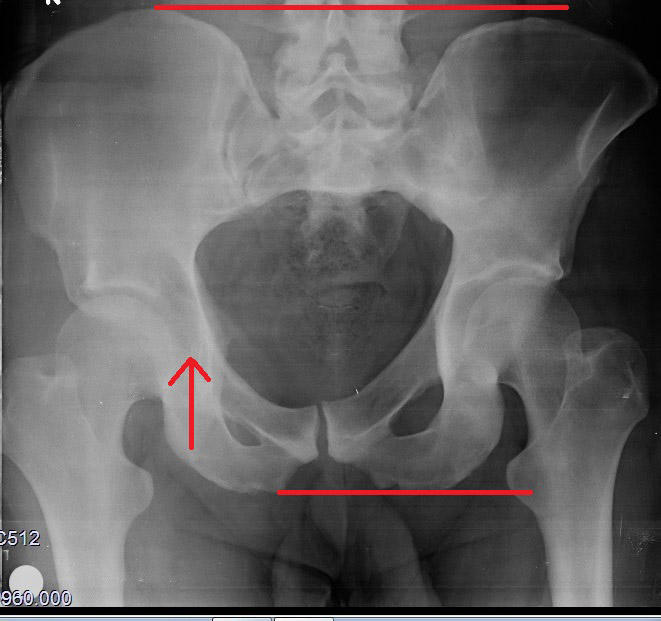

Sol taraftaki resme bakarak sizlere anlatmak istiyorum.Kırmızı kalemle yuvarlak içine alınan kalsiyum tortusunu dorn terapi yöntemiyle dağıtıyoruz.Dağıttıktan sonra o bölgede acıya neden olan siniri (el terapi) yöntemiyle mavi yuvarlağın içersine birkaç maniplasyon hareketiyle yerine getiriyoruz..Pelvis kemiklerini dengeye getirdikten sonra bir kaç dakikalık masaj tekniği ile sorunlu bölge ortadan kalkıyor.Ayağa kalktığınız da daha ilk seansta yüzünüz gülmeye başlıyor ve ayağınızın topuğunu korkusuzca yere basıyorsunuz.Terapi olmak için hala bekliyormusunuz?

Neden leğen kemiği kayar?

Femur kemiğinin origosunun baş kısmı kendi yuvasından aşağıya ya da yukarı doğru kayıyor.Bu kayma sonucunda pelvis kemiğinin yanaklarından biri kayma sonucunda eğim kazanıyor.Eğim gerçekleştiğinde sacrumdan başlayıp lumbal bölgeyi ve sonrasında tüm vertebra disklerini kendi eksenlerinde döndürüyor.

Disklerin içi sıvı kıvamında ve dışa doğru koyulaşıp kabuklaşan bir yapıdadır,bu sayede kolay şekil değiştirebilir. Yukarıdan aşağıya bastırılan yüklerin bir tarafa eğik basması halinde bile bu yumuşaklık sayesinde bir alta yükü eşit dağıtır.Ani ve ters yüklenmeler sonucunda vertebra diskleri intervertebral disk kıkırdağının (pulpeus) etrafında sağ sola hareket edebiliyor.Bir disk döndüğünde nerelere zarar veriyor bunu bir disk kaydığında neler olur butonuna tıklayarak öğrenebilirsiniz